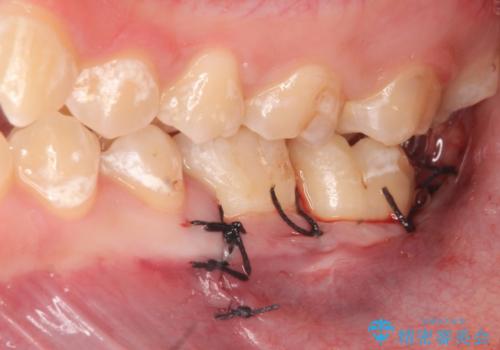

左下7の虫歯は深く、また歯冠高径も低かったため、歯冠長延長術を行いました。

術後歯肉の回復を待ち、左下6はセラミックインレー、左下7はオールセラミッククラウンにて補綴しました。